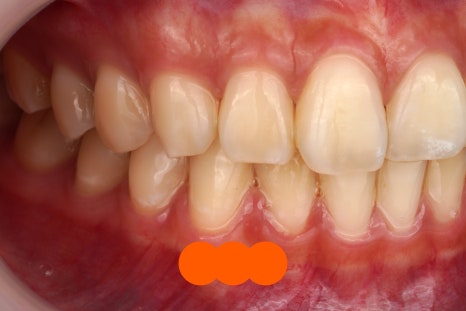

아까 말씀드렸죠

눈으로는 모른다고.

이렇게 고화질 카메라로 찍은 다음

눈앞에서 바로 확대해서 확인시켜드립니다.

이렇게나 자주 떼고 있는데

노하우가 있겠죠 당연히?

투스젬 제거도

노하우가 필요합니다.

어떤 노하우가 필요할까요?

이 글에서 알아보시죠.